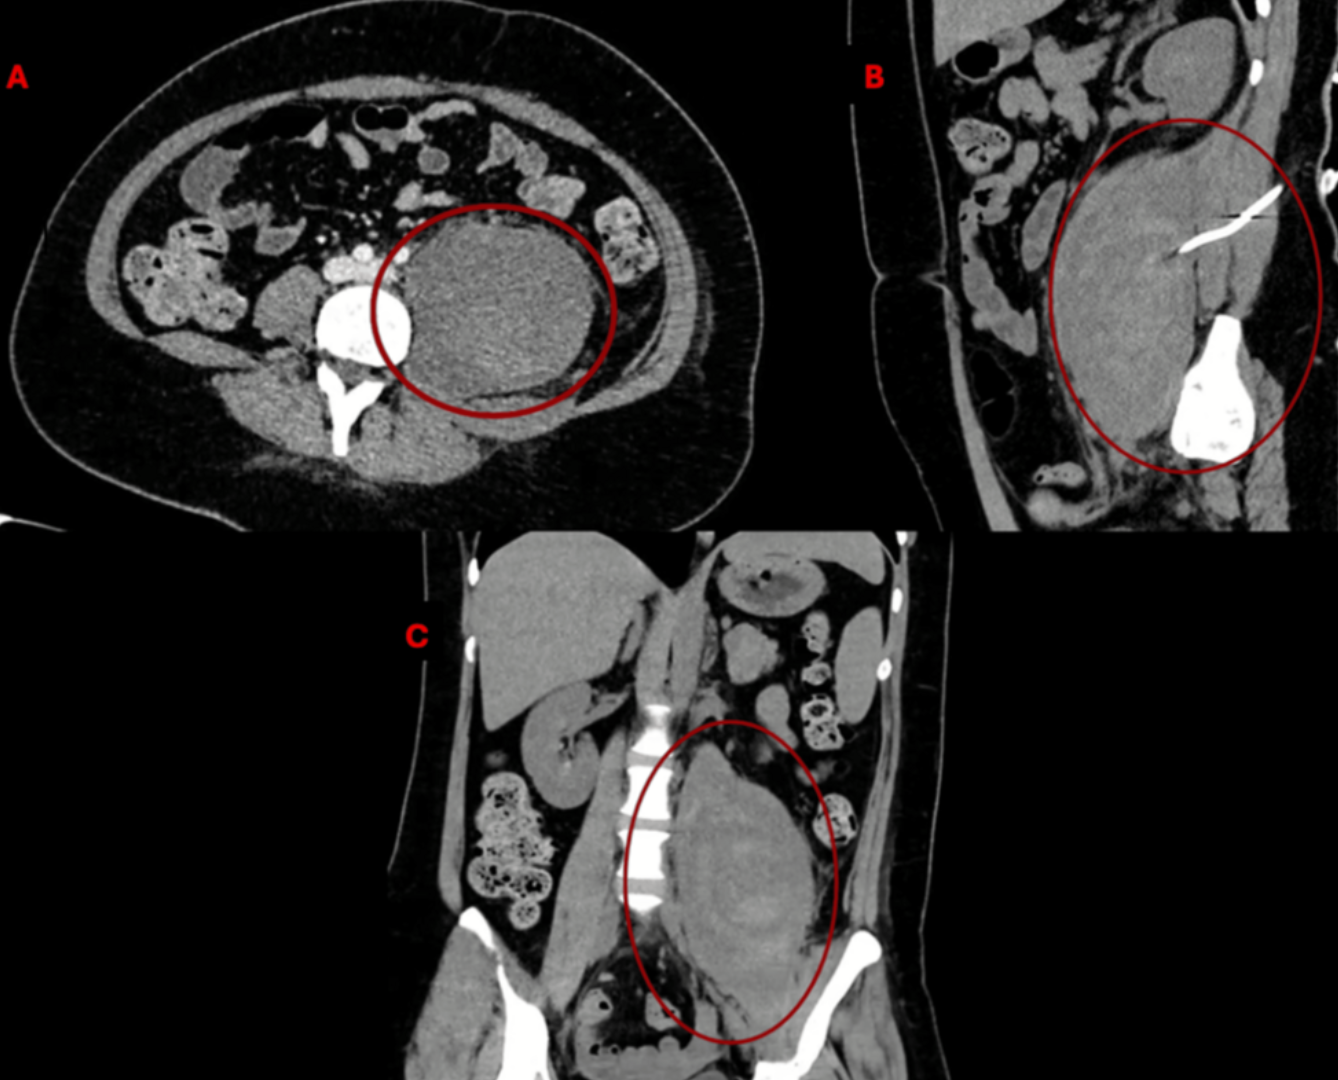

Пациентке провели КТ, МРТ и КТ с контрастом. Была выявлена гематома левой подвздошно-поясничной мышцы объемом 896 мл, сдавливавшая бедренный нерв. Других отклонений не обнаружено. Для дренирования установлен катетер. Спустя три месяца гематома уменьшилась до 257 мл. Боль и слабость в левой ноге разрешались постепенно. Спустя шесть месяцев у пациентки сохранялась парестезия в ноге, боль — 3 из 10 баллов, сила конечности — 4 из 5 баллов. В левой подвздошно-поясничной мышце обнаружена остаточная жидкость объемом 43 мл.